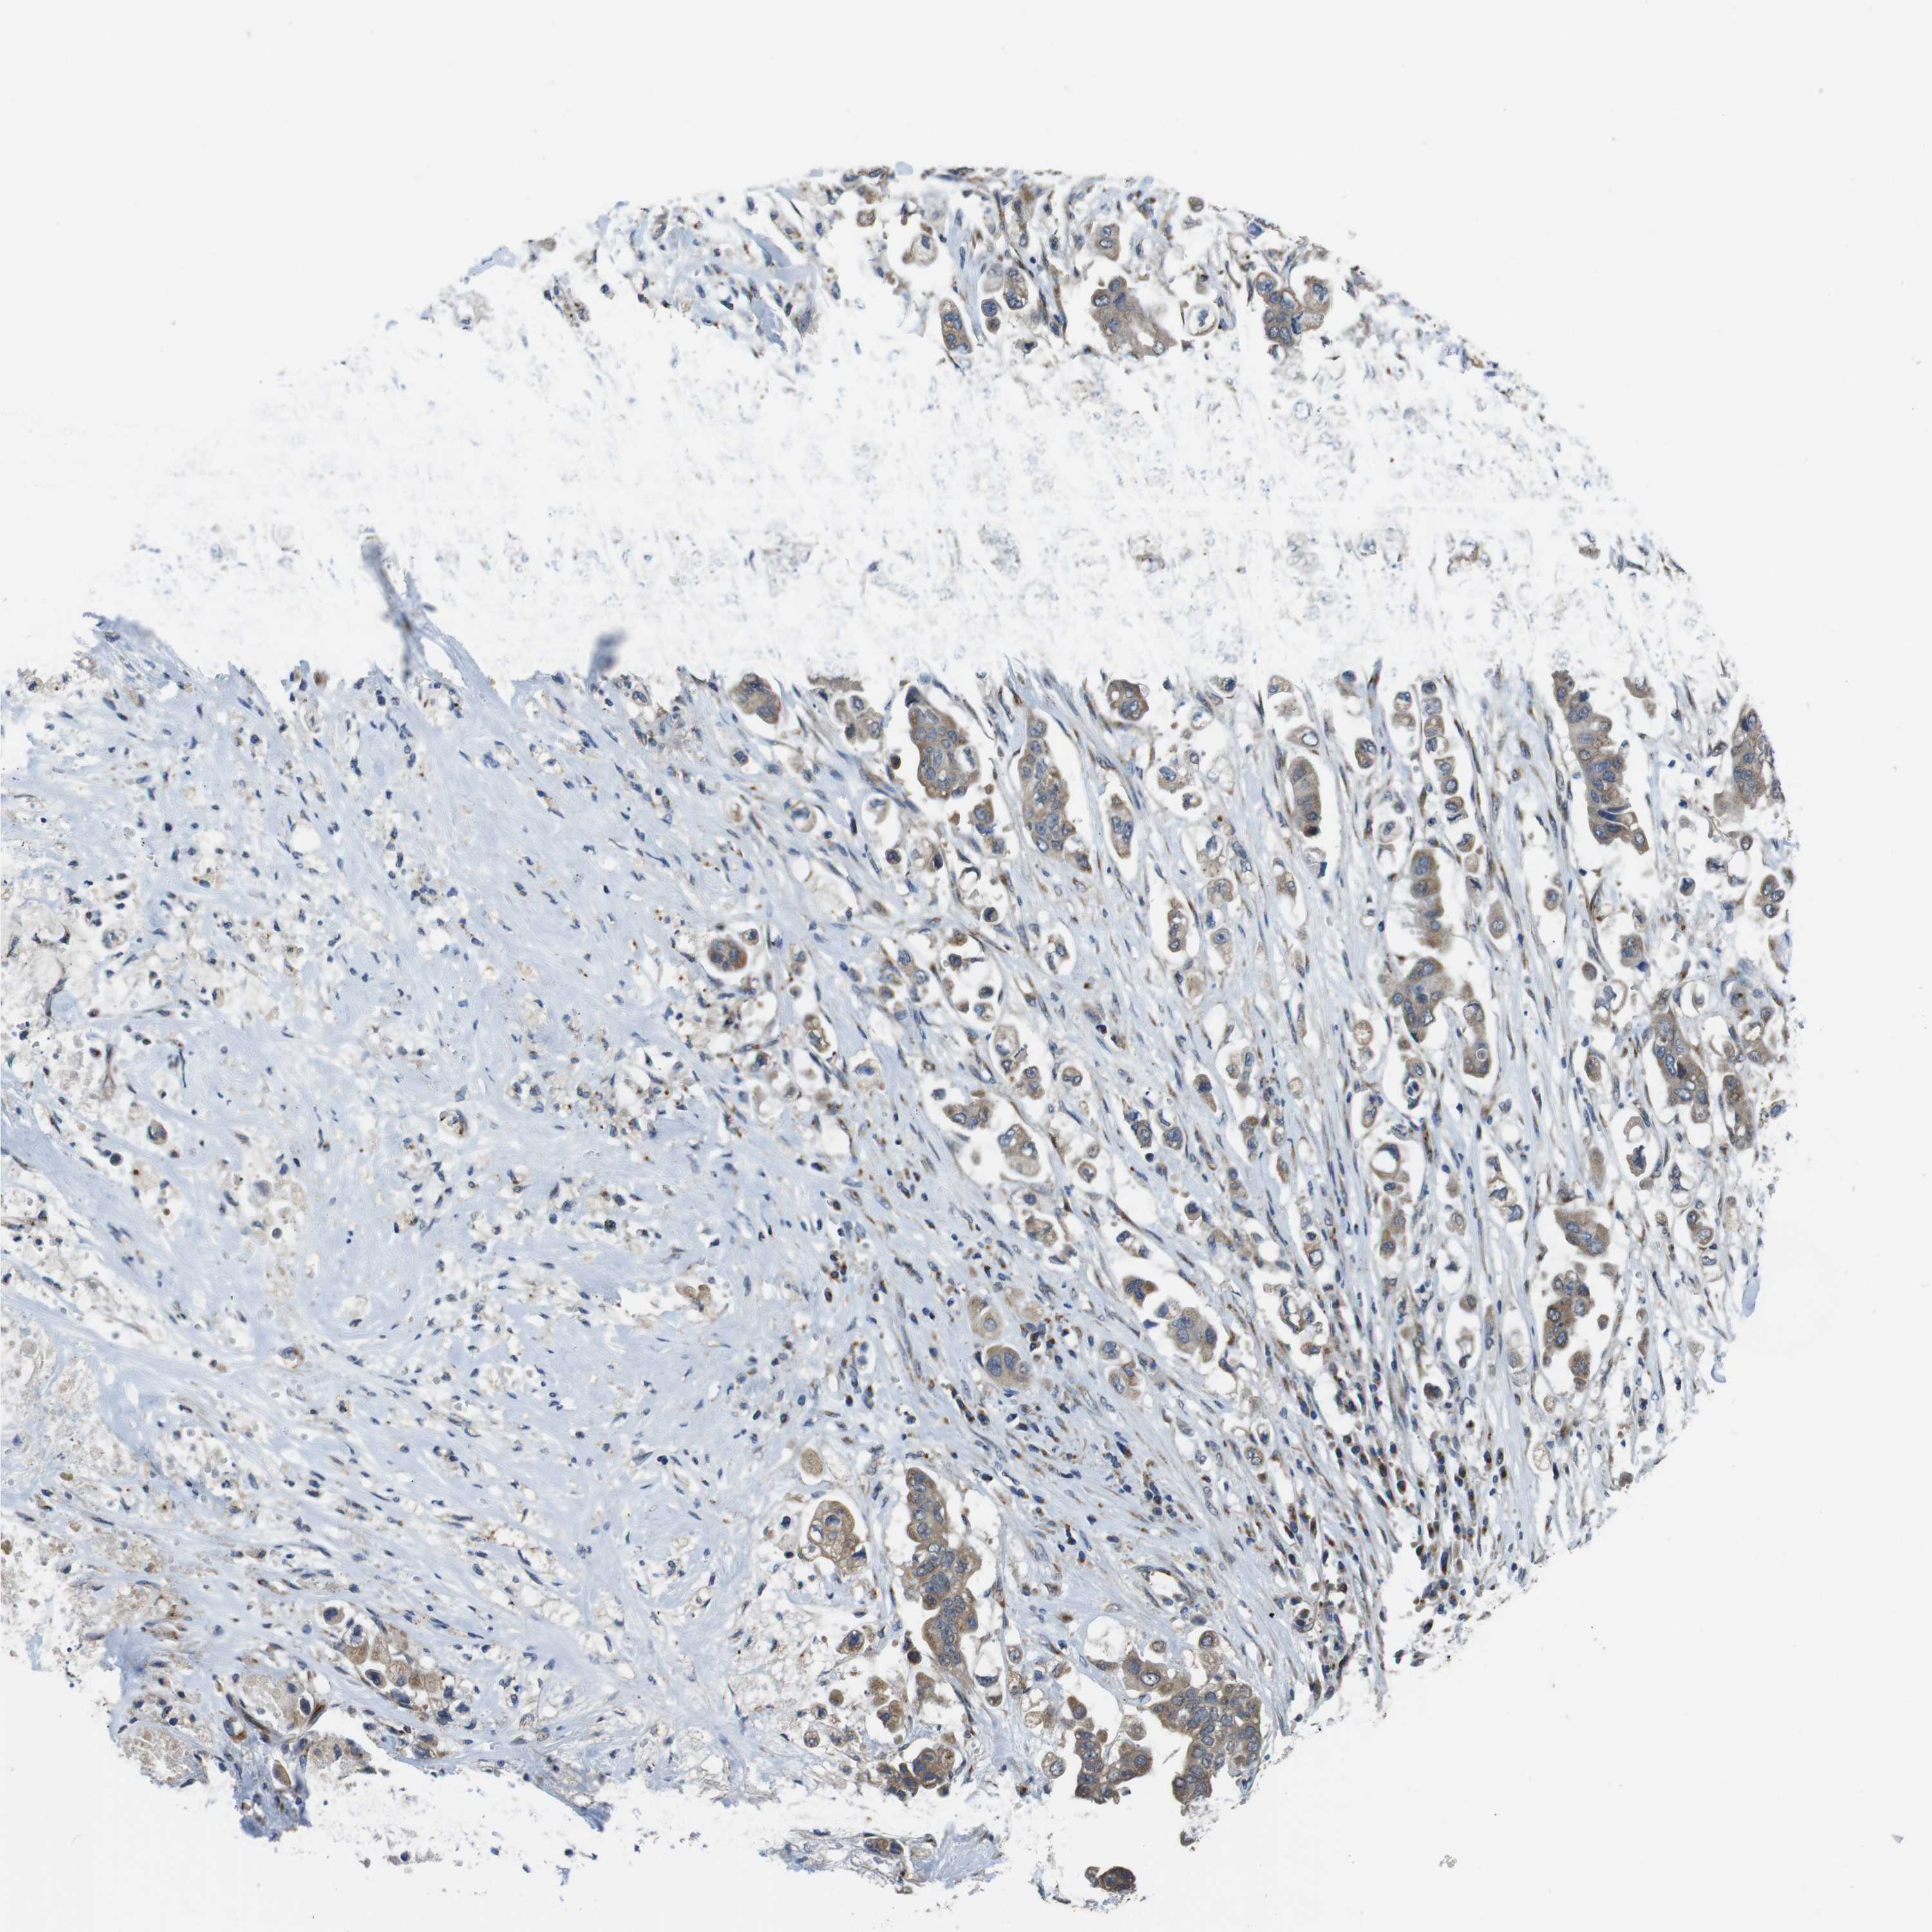

STOMACH CANCER - Protein expressioni

A mouse-over function shows sample information and annotation data. Click on an image to view it in a full screen mode. Samples can be filtered based on level of antibody staining by selecting one or several of the following categories: high, medium, low and not detected. The assay and annotation is described here.

Note that samples used for immunohistochemistry by the Human Protein Atlas do not correspond to samples in the TCGA dataset.

Antibody stainingi

Antibody staining in the annotated cell types in the current human tissue is reported as not detected, low, medium, or high, based on conventional immunohistochemistry profiling in selected tissues. This score is based on the combination of the staining intensity and fraction of stained cells.

Each image is clickable and will lead to virtual microscopy that enables deeper exploration of all samples and also displays staining intensity scores, fraction scores and subcellular localization as well as patient and tissue information for each sample.

Antibody HPA059131

Antibody CAB009936

Staining

High

Medium

Low

Not detected

Intensity

Strong

Moderate

Weak

Negative

Quantity

>75%

75%-25%

<25%

None

Location

Nuclear

Cytoplasmic/membranous

Cytoplasmic/membranous,nuclear

Adenocarcinoma, NOS

Adenocarcinoma, High grade